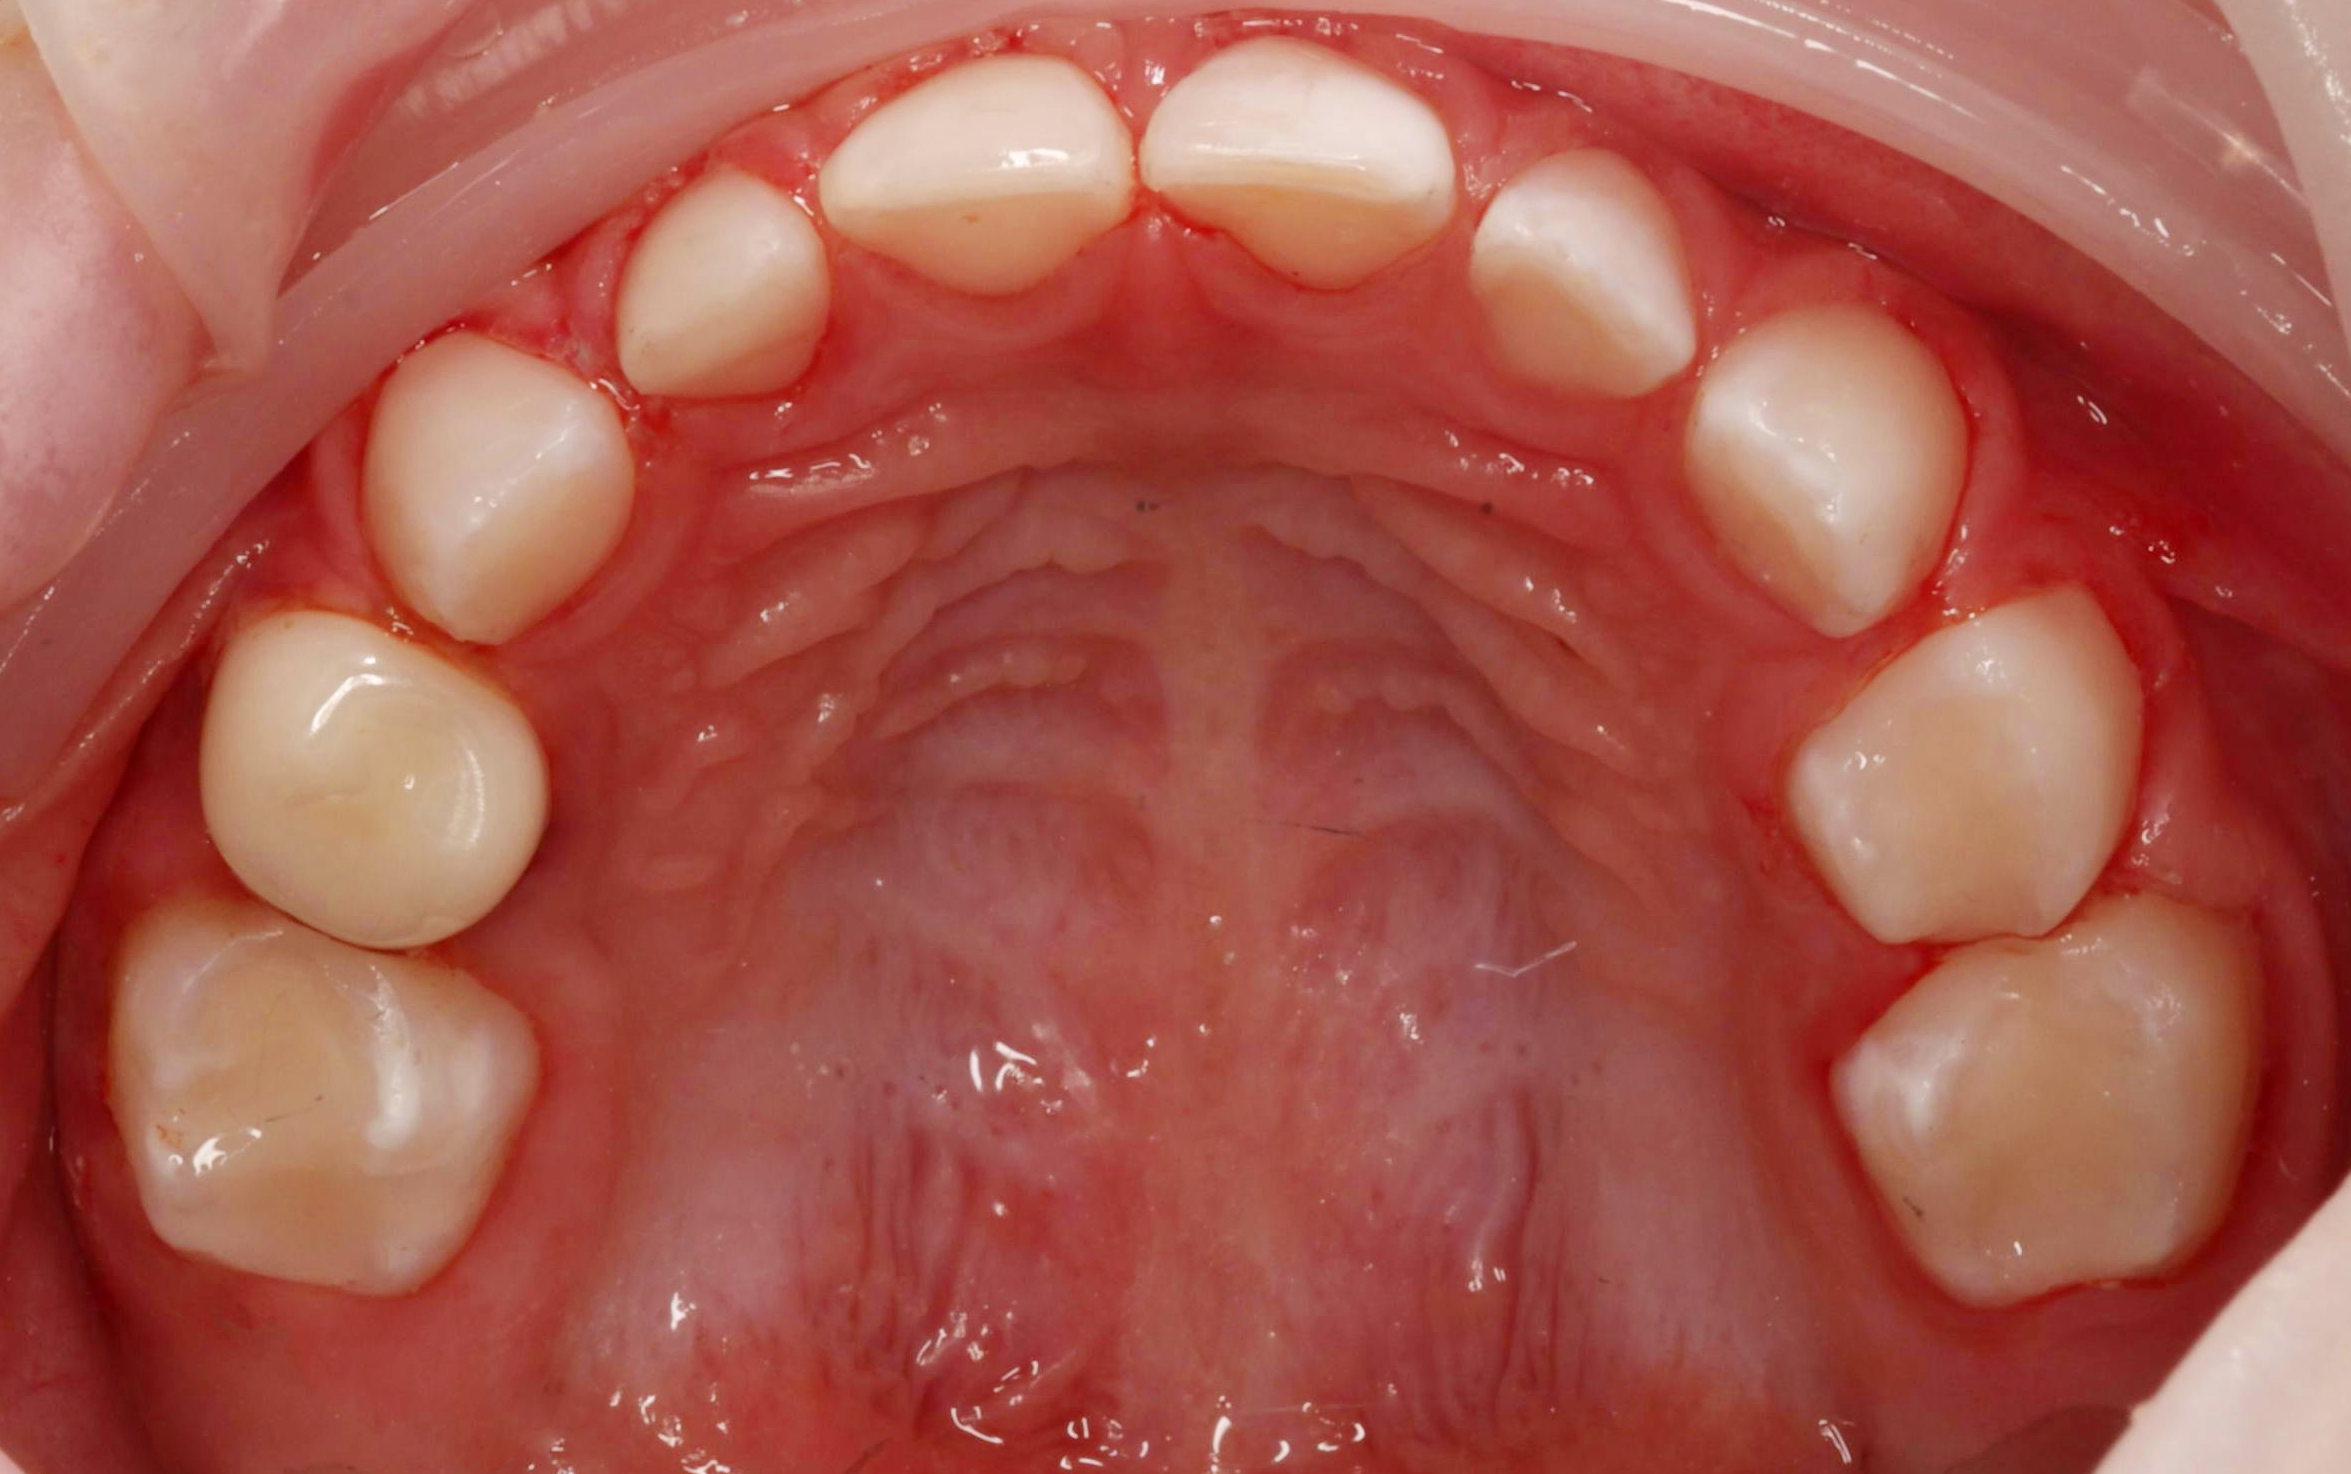

Специализация: лечение кариеса, пульпита и периодонтита временных зубов, эстетическая реставрация и профилактика